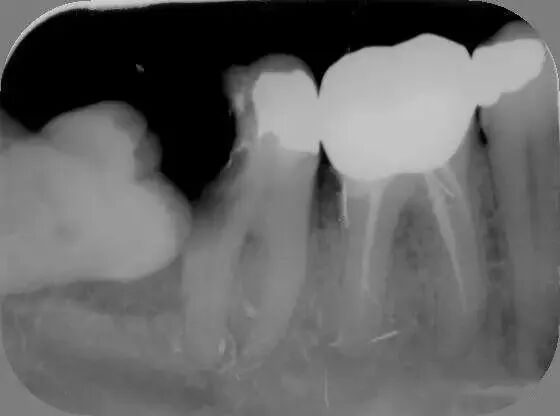

3、邻牙龋坏和牙周炎

智齿与邻牙之间有小的缝隙存在,食物残渣可以留存,长时间就可以导致邻牙发生龋坏和或牙周炎,如图所示: